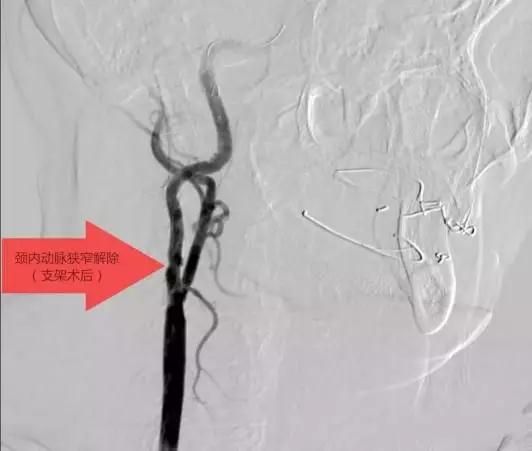

2018年8月

赤壁市首例頸動(dòng)脈狹窄介入手術(shù)在我院順利完成,填補(bǔ)了我市在頸動(dòng)脈介入治療方面的空白。